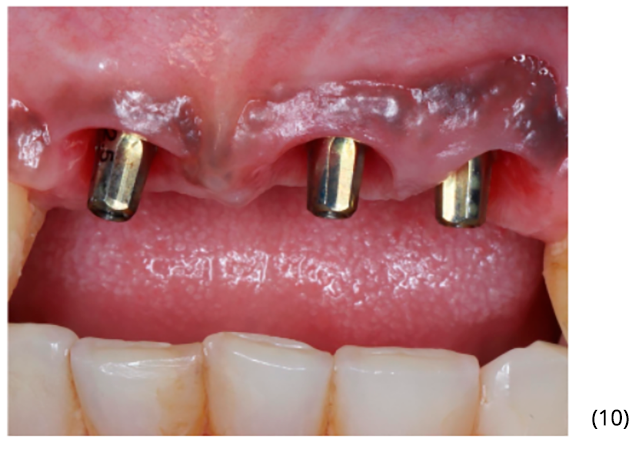

Utilizamos três munhões do tipo Ideale – Implacil De Bortoli de altura 3.3×2.5×4 mm para confecção das próteses do tipo parafusada (imagens 10 e 11). A foto final foi no acompanhamento de seis meses, onde podemos observar ótima estabilidade do tecido peri-implantar (imagem 12).